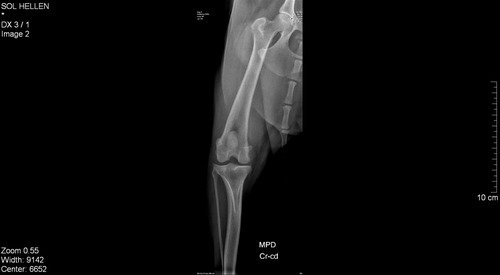

Abaixo está as imagens do raio X dela.

Ruptura de ligamento do joelho, correção cirúrgica, não há outro tratamento, sem isso o animal vive com dor crônica pois vai lesionar os meniscos, alta chance de artrose se desenvolver mais rápido e vai forçar a outra pata pra acontecer a mesma coisaA cirurgia pra corrigir isso chama TPLOValor estimado a vista 2700Material 550Anestesia 650Cirurgia 1500